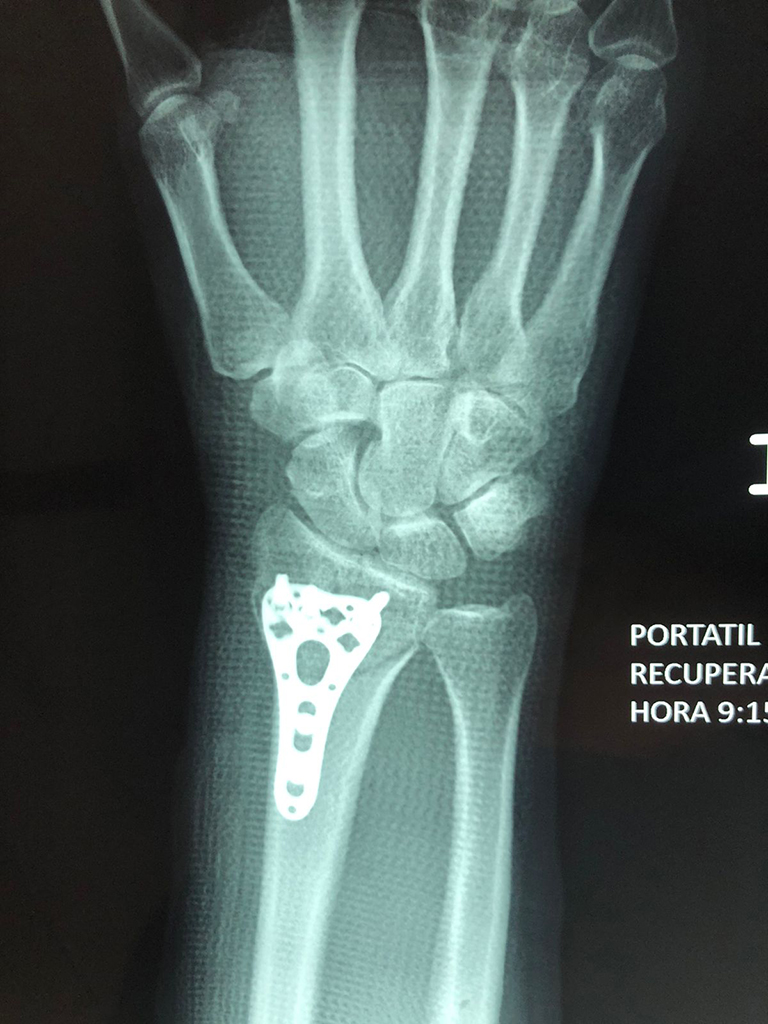

Húmero - Cirugías de Muñecas y Manos

Los procedimientos más comunes en cirugía de la mano son aquellos destinados a reparar traumatismos, incluyendo lesiones de tendones, nervios, vasos sanguíneos, y articulaciones; huesos fracturados; y quemaduras, cortes, y otros daños de la piel.